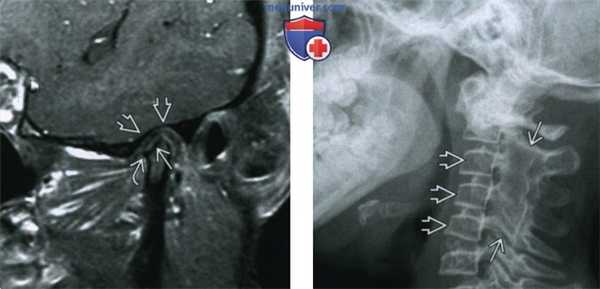

(Слева) При МРТ Т1ВИ FS с КУ в кососагиттальной проекции у пациентки 21 года с ювенильным идиопатическим артритом определяется уменьшенный мыщелок нижней челюсти с деформированными склерозированными краями с низкой интенсивноаью сигнала. Суставная ямка плоская и расширенная. Контрааное усиление, обусловленное воспалением, отсутствует. Отмечается небольшой остеофит в передних отделах (признак вторичного остеоартроза).

(Справа) На рентгенограмме в боковой проекции у девочки 13 лет, страдающей ювенильным идиопатическим артритом, определяются «классические» изменения: слияние задних отделов С2-С5 и уменьшение передне-заднего размера их тел.